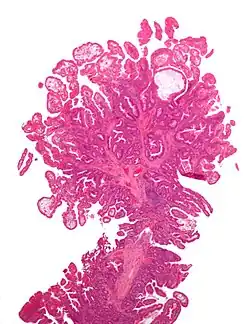

| Tubular adenoma | 2% at 1.5 cm[12] | Low to high grade dysplasia[13] | Over 75% of volume has tubular appearance.[14] |

|

Micrograph of a tubular adenoma, the most common type of dysplastic polyp in the colon -